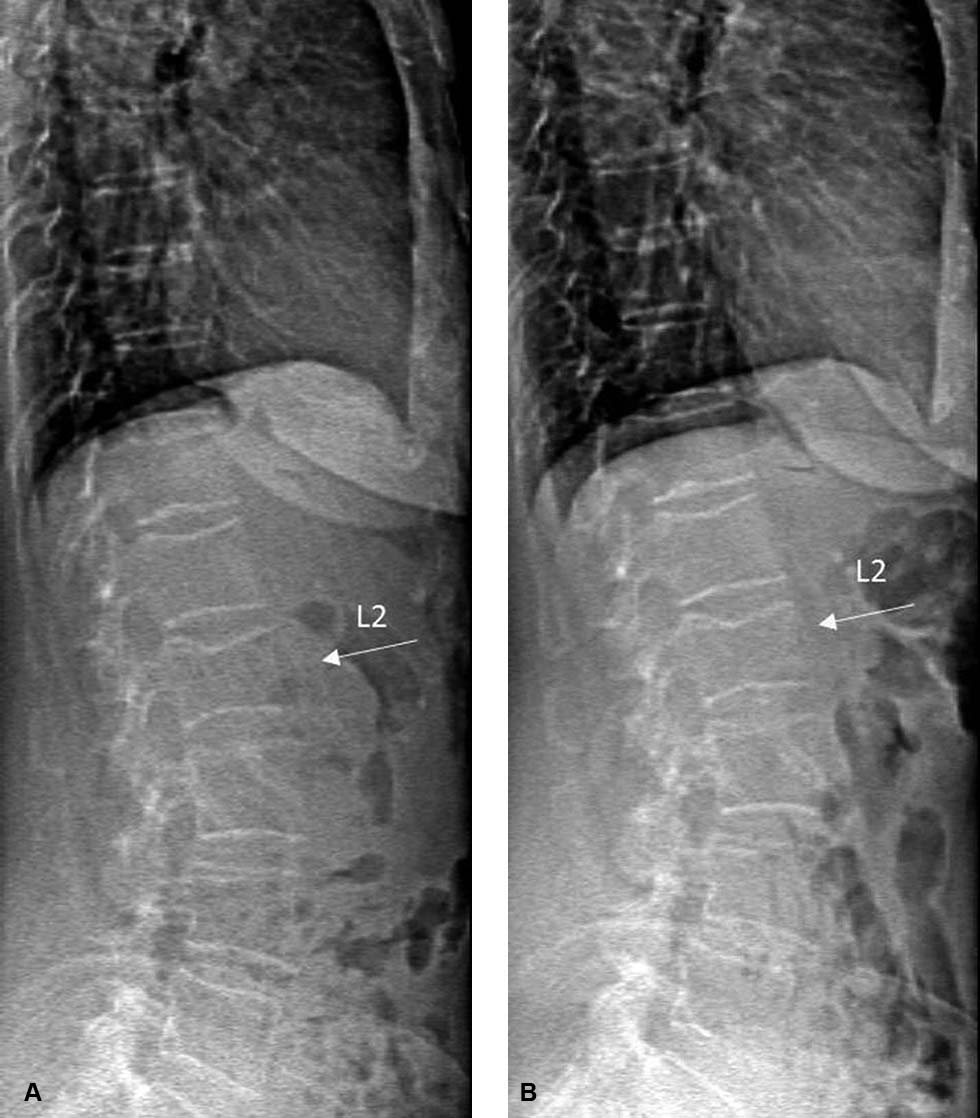

Een 71-jarige vrouw met primaire osteoporose en een klinische wervelinzakkingsfractuur van de tweede lendenwervel wordt vanaf 2012 vijf jaar lang behandeld met denosumab omdat zij orale bisfosfonaten niet verdraagt. Eind 2017 stopt zij met denosumab omdat het fractuurrisico als laag wordt ingeschat. De botmineraaldichtheid (BMD) van de heuphals en de lumbale wervelkolom (LWK) is verbeterd ten opzichte van 2012 en de T-score van heuphals en LWK is –2,0, wat erop wijst dat er geen sprake meer is van osteoporose. Uit de vertebral fracture assessment met dual-energy x-ray absorptiometrie (DEXA-VFA) blijkt dat zich geen nieuwe wervelfractuur heeft ontwikkeld [figuur 1].

In 2018, acht maanden na de laatste denosumabinjectie, bezoekt patiënte haar huisarts vanwege acute pijn in de rug, ontstaan tijdens een wandeling met een lichte rugzak. Omdat de pijnklachten aanhouden, laat de huisarts een röntgenfoto van de thoracale en lumbale wervelkolom maken. Daarop zijn inzakkingsfracturen te zien van de wervellichamen Th12, L2, L3 en L4. De fracturen van Th12, L3 en L4 waren op de opnames uit 2017 nog niet aanwezig [figuur 2].